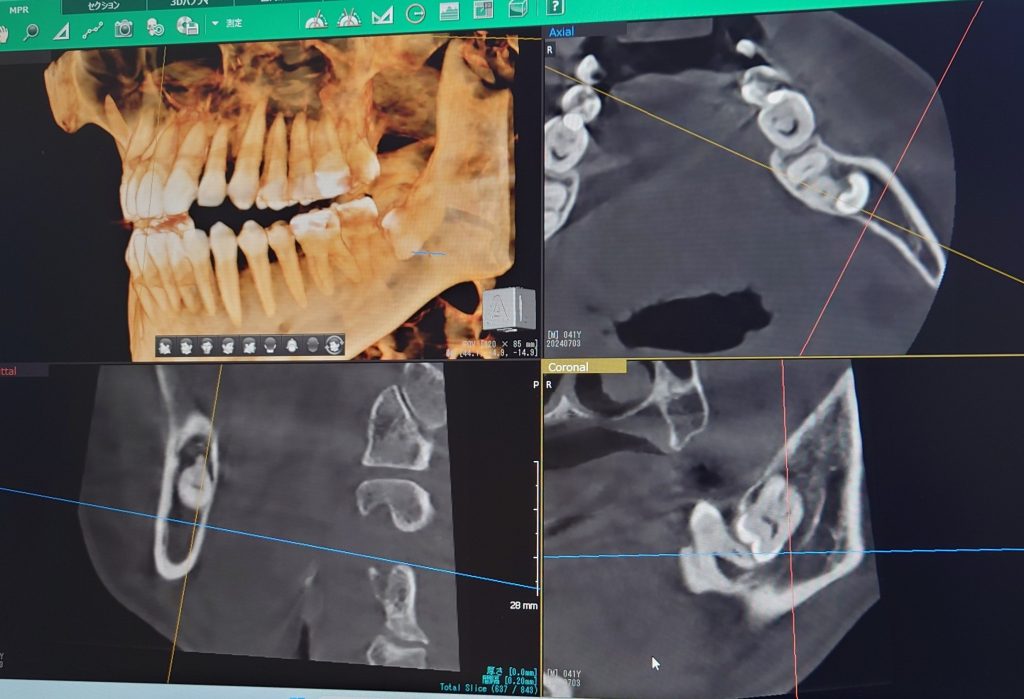

おそらく歯科用CTを導入している先生が増えてきたからではないでしょうか。

当院でも最新の歯科用CTを導入し診断し、実際に施術していると、今までとは比べ物にならないほどの処置のスムーズさを感じています。それは術前のイメージトレーニングが明確にできるからだと思います。

当院で抜歯できない親知らずは骨の中を通っている下歯槽神経と親知らずの根の部分が明らかに接しているケースです。CT撮影を行い、神経と接しているケースは大学病院などの口腔外科へ紹介致します。

下の親知らずの根の先は下歯槽神経という神経に近接しています。場合によっては神経と親知らずの根の先が触れているケースがあり、親知らずの抜歯の際に親知らずが揺らされる事によりこの神経を圧迫してしまったり、傷つけてしまう事で、唇にしびれが残ってしまうケースがございます。CT撮影を行い、下歯槽神経と親知らずの根が近接している場合はリスクを考慮したうえで、高次医療機関への受診をすすめる場合もあります。

横にはえて大部分が歯肉の下に埋まっている下の親知らずを安全に抜歯するためにCTを撮影し下歯槽神経との関係を調べた後に抜歯した場合、3割負担で8000円程度です。